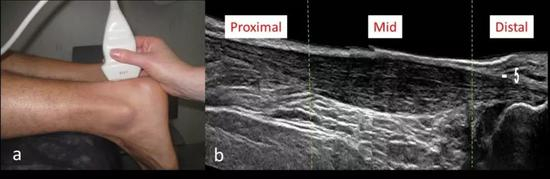

● 如果病史典型,且经过保守治疗康复有效,通常不需要辅助检查。X线对于诊断跟腱病没有帮助,超声和核磁共振有助于判断跟腱结构,常用于辅助检查;